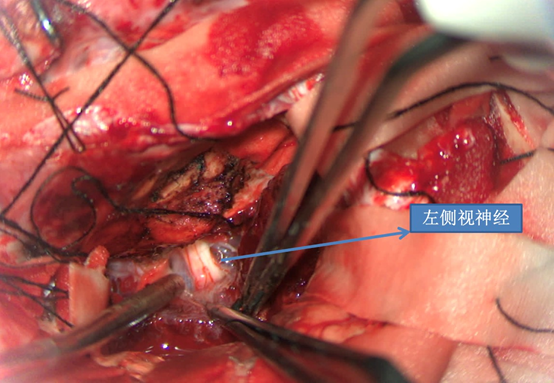

前颅窝底脑膜瘤常起源于前颅底筛骨筛板处的硬膜,瘤体多为双侧生长,少数为偏侧生长,女性稍多于男性。肿瘤可累及鸡冠和蝶骨平台的任何区域,是前颅窝肿瘤中最多见的一种。因为肿瘤位于前颅窝底,额叶在功能上属于“哑区”,患者就诊发现肿瘤时瘤体多已巨大。主要症状可有颅内压增高症状、视力减退、癫痫以及精神症状等。该患者主因“左眼失明10个月,头痛3个月”就诊。术中采用双额冠状开颅,左侧为主,由于肿瘤体积巨大,术中切除少许薄层额叶脑组织,边离断基底、边瘤内减压,分块切除肿瘤,最终探查肿瘤基底主要位于鸡冠、筛板、蝶骨平台、鞍结节、前床突处硬膜,术中见肿瘤供血主要来源于前颅窝底硬膜及大脑前动脉分支,术中仔细辨认供血动脉、过路血管,大脑前动脉及其分支保护完好,术中见视神经、视交叉受压明显,尤其是左侧视神经已缺血苍白,最终达Simpson II级切除。术者体会,该患者术前行多模态重建,可见瘤表数条粗大的静脉,术中切莫过早离断肿瘤的引流静脉,以防因引流不畅致瘤体肿胀出血;术前行多模态重建,利于鉴别供血动脉、过路血管,早期离断供血动脉更利于肿瘤切除;该类肿瘤基底一般较为广泛,不能盲目离断基底,尤其是近鞍结节处,可以于中线处离断基底,进入第一间隙后向两侧探查并保护视神经,待充分缩小瘤体看清楚毗邻的血管神经后再将其完全切除;术毕做好多层颅底重建以防脑脊液漏。另外,该患者术前左眼失明已达10个月,术后第1天即有光感,术后1月复查左眼视力可达50cm内数指,这在临床中非常少见,对于此类病人,不要轻易放弃挽救视力的任何机会。